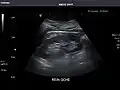

Right kidney -